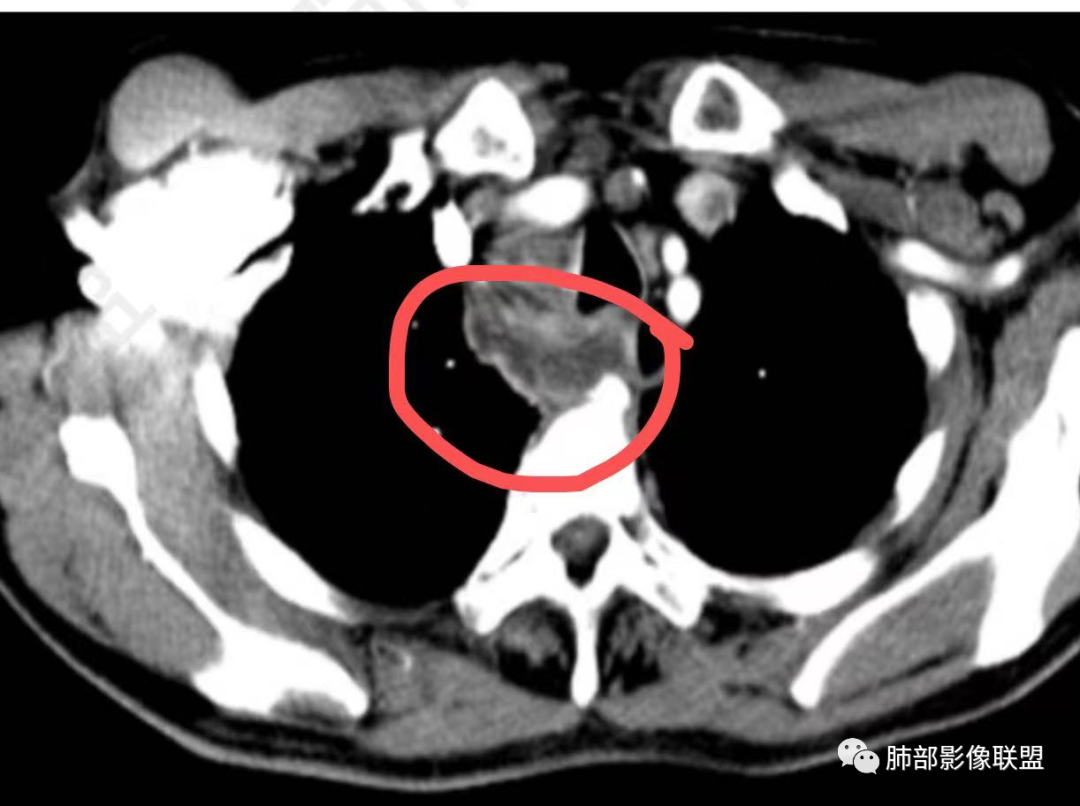

病理切的是一个淋巴结,在同一个既发现了肉芽肿,也发现了干酪样坏死,还发现了淋巴瘤,同一个淋巴结里面。

2、影像特点:双肺多发结节及条索影,边缘清晰,右肺上叶可见网格影,右侧胸腔少量积液;颈部、纵膈及腹部多发淋巴结肿大,大部淋巴结强化不均,呈环形强化,内部见低密度坏死区,部分淋巴结坏死不明显,尤其是腹部淋巴结密度较均匀。

3、综上:病人低热不具有特异性,结核及淋巴瘤都可以存在。胸部影像、治疗经过及实验室检查更支持结核,但是全身广泛淋巴结肿大,在继发性肺结核中并不常见,EB病毒核酸阳性,虽然不具有特异性,还是应该警惕淋巴瘤。

最终病理结果证实;淋巴结结核和T淋巴母细胞淋巴瘤(非霍奇金淋巴瘤)并存。